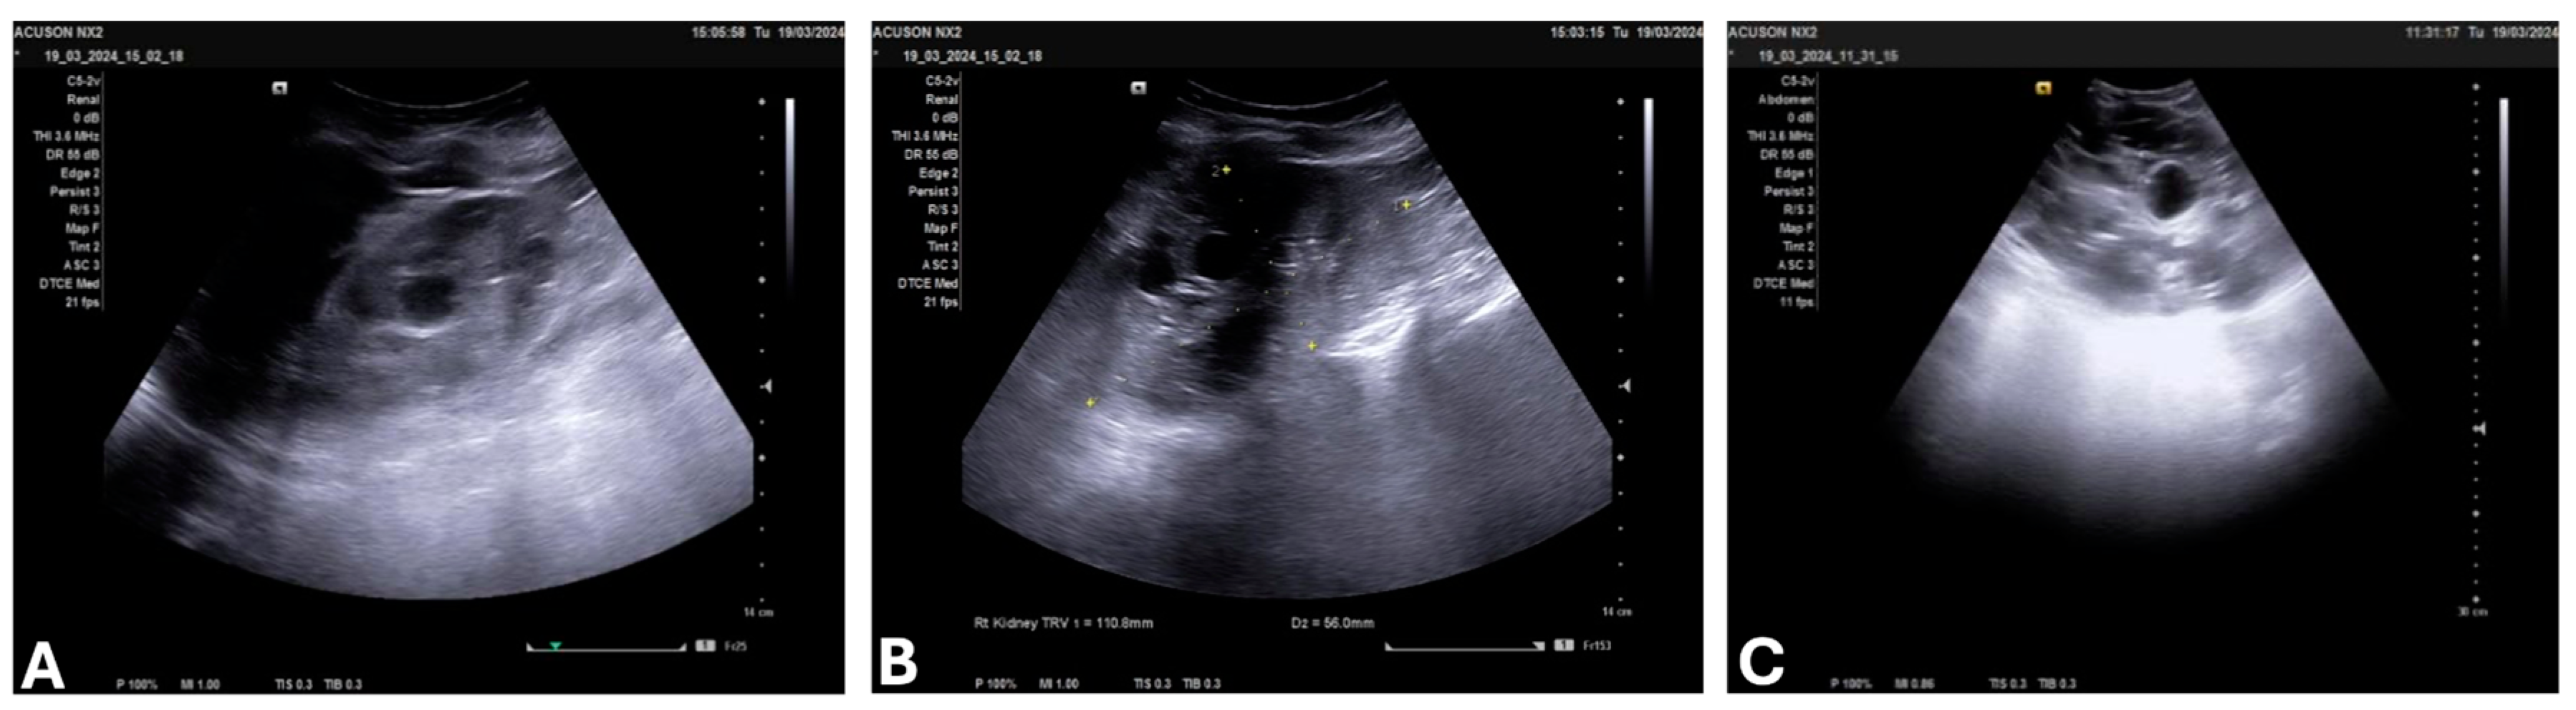

3.4. Laboratory Findings, Imaging, and Stage of ADPKD